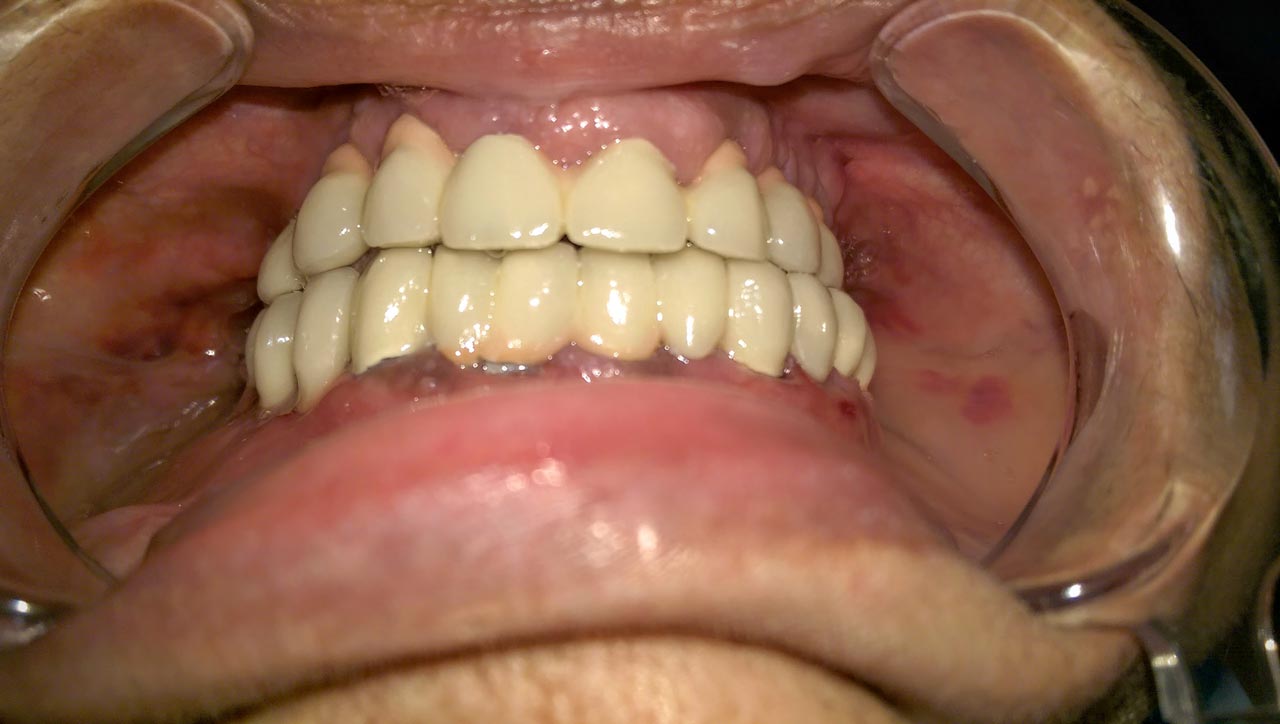

Teljes fogatlanság helyreállítása 2 nap alatt

Teljes fogatlanság helyreállítása 2 nap alatt azonnal terhelhető svájci IHDE implantátumokkal és PMMA műanyag hidakkal. Intraorális szkennerrel vettünk lenyomatot az implantáció után, és erre a digitális mintára készítette el a fogtechnika a hidak digitális tervezését, majd faragta ki műanyagból. Ezt a gyors munkát az azonnal terhelhető implantátumok és a digitális lenyomat, tervezés segítségével tudtuk megcsinálni mindössze 2 nap alatt. Dr. Kelemen Péter és a Symbion Fogtechnika munkája.